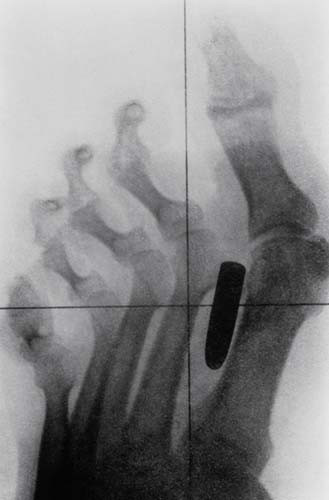

Galerinin tamamı için tıklayınızBir erkeğin orta işaret parmağı ve orta parmak kemiklerine saplanmış bir çivi.

Bir erkeğin orta işaret parmağı ve orta parmak kemiklerine saplanmış bir çivi.